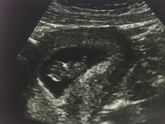

Сегодня прослезилась на УЗИ, когда услышала сердцебиение. Моё сокровище уже двигает ручками и ножками. Дай Бог каждому, кто желает ощутить это счастье!